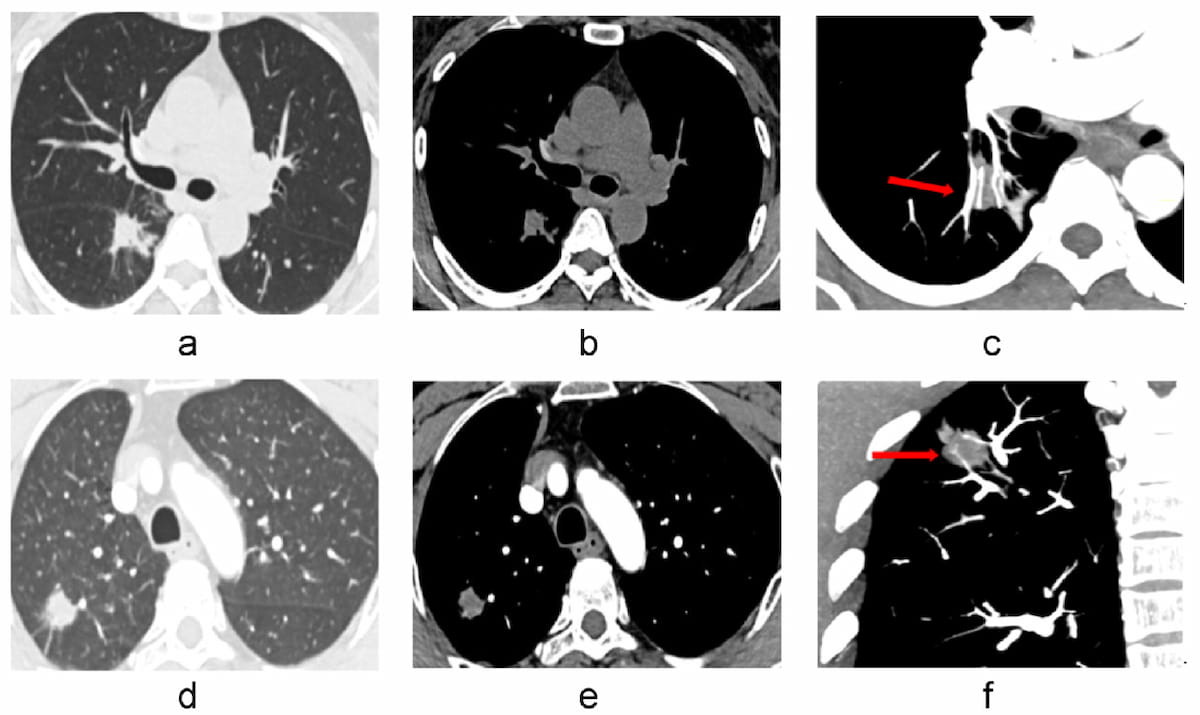

Emerging research shows that a multiple time-series deep learning model assessment of CT images provides 20 percent higher sensitivity than a delta radiomic model and 56 percent higher sensitivity than a clinical model for prognostic evaluation of ground-glass nodules.